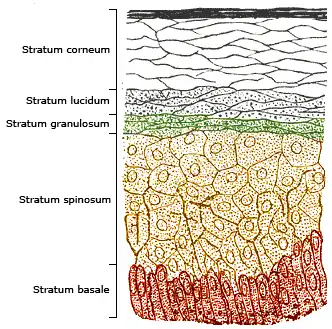

Melanin, specifically the sub-type eumelanin, is a biomolecule consisting of linked molecules of oxidized amino acid tyrosine. It is produced by cells called melanocytes in a process called melanogenesis. In the skin, melanin is located in the bottom layer (the stratum basale) of the skin's epidermis. Melanin can be permanently incorporated into the skin, resulting in dark skin, or else have its synthesis initiated by exposure to UV radiation, causing the skin to darken as a temporary sun tan. Eumelanin is an effective absorbent of light; the pigment can dissipate over 99.9% of absorbed UV radiation.[49] Because of this property, eumelanin is thought to protect skin cells from sunlight's ultraviolet A (UVA) and ultraviolet B (UVB) radiation damage, reducing the risk of skin tissue folate depletion, preventing premature skin aging and reducing the risks of sunburn and skin cancer.[50] Melanin inhibits UVB-powered vitamin D synthesis in the skin. In areas of the world not distant from the equator, abundant, year-round exposure to sunlight means that even dark-skinned populations have adequate skin synthesis.[51] However, when dark-skinned people cover much of their bodies with clothing for cultural or climate reasons, or are living a primarily indoor life in urban conditions, or live at higher latitudes which provide less sunlight in winter, they are at risk for vitamin D deficiency.[25][52] The last cause has been described as a "latitude-skin color mismatch".[51]

Vitamin D3 is produced photochemically from 7-dehydrocholesterol in the skin of most vertebrate animals, including humans.[180] The skin consists of two primary layers: the inner layer called the dermis, and the outer, thinner epidermis. Vitamin D is produced in the keratinocytes of two innermost strata of the epidermis, the stratum basale and stratum spinosum, which also can produce calcitriol and express the vitamin D receptor.[181] The 7-dehydrocholesterol reacts with UVB light at wavelengths of 290–315 nm. These wavelengths are present in sunlight, as well as in the light emitted by the UV lamps in tanning beds (which produce ultraviolet primarily in the UVA spectrum, but typically produce 4% to 10% of the total UV emissions as UVB). Exposure to light through windows is insufficient because glass almost completely blocks UVB light.[182] In skin, either permanently in dark skin or temporarily due to tanning, melanin is located in the stratum basale, where it blocks UVB light and thus inhibits vitamin D synthesis.[49]